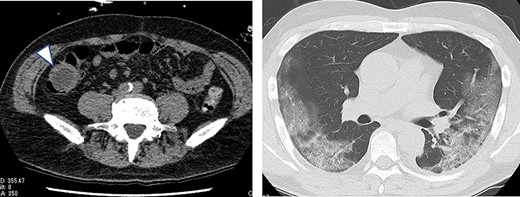

A 63-year-old male who had fever and dyspnea visited a medical institution. Both antigen and polymerase chain reaction (PCR) tests for SARS-CoV-2 were positive and he was hospitalized for treatment. Nine days after admission, he was transferred to our hospital due to deteriorating respiratory condition. After admission to our hospital, ventilator management and steroid administration were performed. After 3 days, his respiratory condition improved and he was able to withdraw from the ventilator. Computed tomography (CT) taken for observation of lung disease coincidentally showed cystic lesions in the right abdomen (Fig. 1). He had no abdominal symptoms at this time. The patient was discharged on the 18th day of hospitalization. He had diarrhea from the 15th day after discharge and abdominal pain from the next day. He consulted his family doctor on the 17th day because the abdominal pain persisted. CT examination revealed enlargement of cystic lesion and intussusception of the right colon (Fig. 2). The patient was transferred to our hospital as an emergency case. Physical findings showed fever with a body temperature of 38°C and tenderness in the right lower abdomen. Blood test showed an inflammatory reaction with a white blood cell count of 13 000/μl and C-reactive protein of 2 mg/dl. The SARS-CoV-2 PCR testing was negative. We performed emergency surgery on the same day.

Plain CT taken when the patient was transferred to our hospital for abdominal pain; the cystic lesion had increased in size (arrowhead) and showed intussusception.